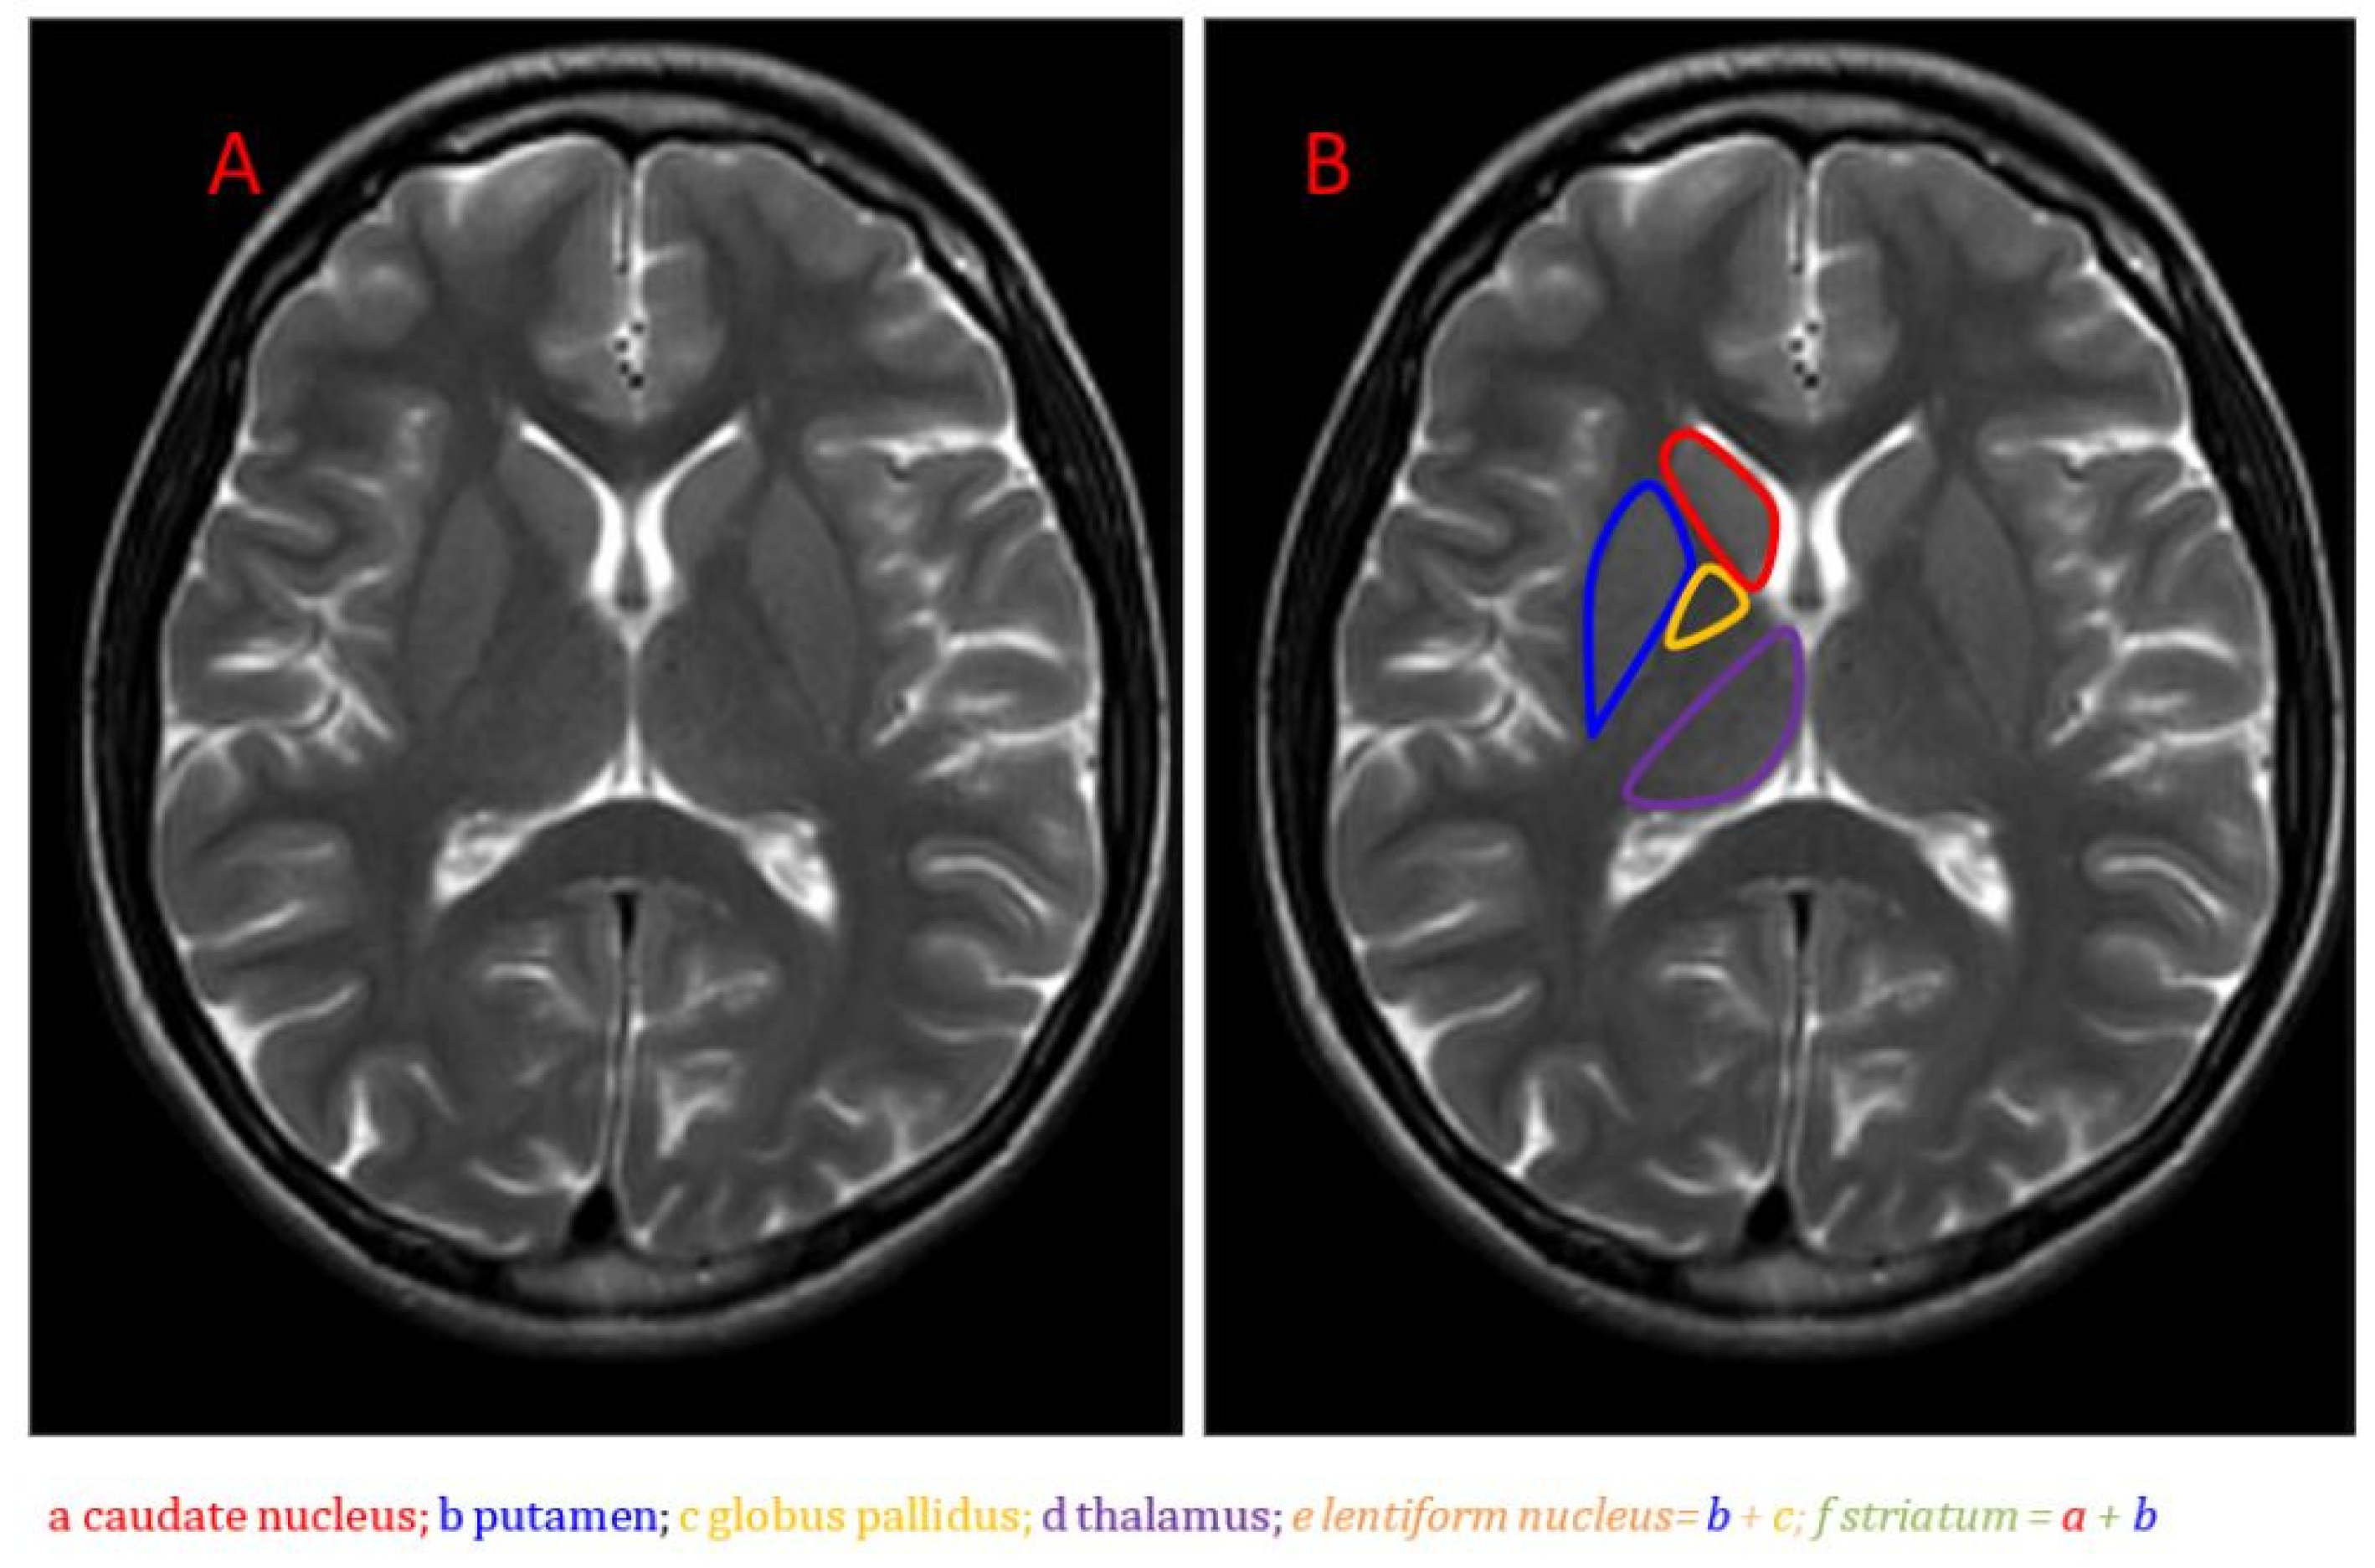

Recently, attention has turned to the basal ganglia—an interconnected group of subcortical nuclei known to regulate sleep–wake drive, motivation, motor control, and effort-based decision making [5]. Comprised of structures, including the striatum, pallidum, substantia nigra, and subthalamic nucleus, the basal ganglia receive input from and signal to numerous cortical areas [6] (Figure 1; [7]). This strategic placement at the intersection of the limbic, cognitive, and motor loops suggests the basal ganglia may orchestrate diverse aspects of behavior and physiology relevant to fatigue.

Figure 1.

Anatomical MRI of the basal ganglia in the axial plane on T2-weighted imaging: (A) Unlabeled image; (B) Image with caudate nucleus, putamen, globus pallidus, and thalamus labeled [7].